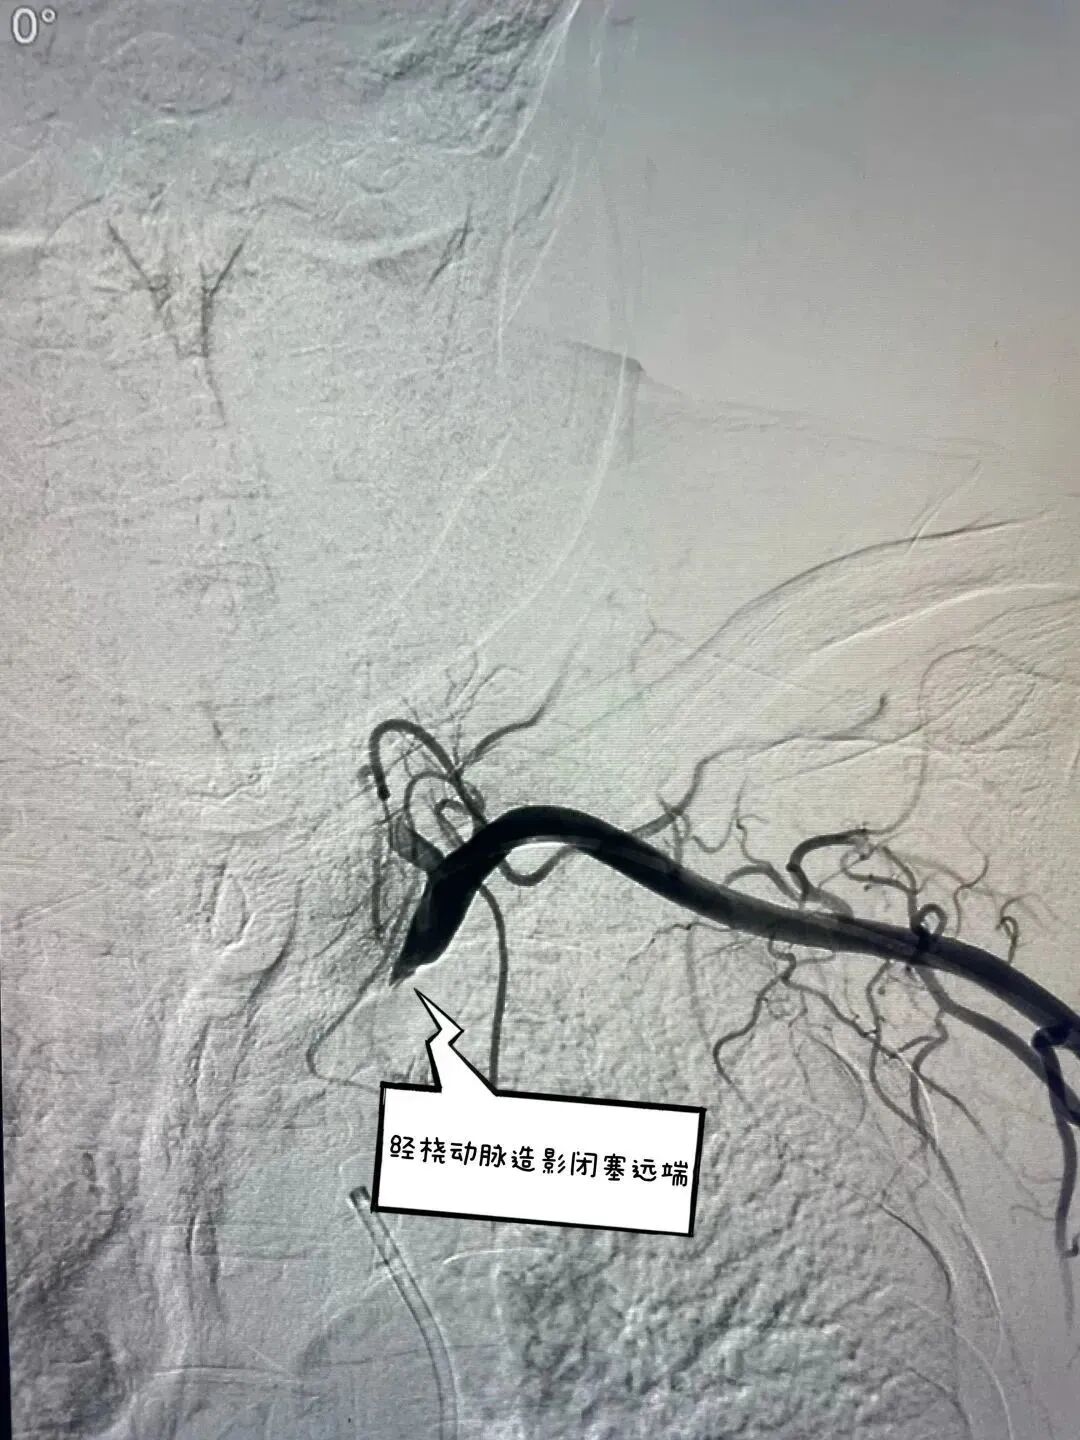

主动脉弓造影提示左侧锁骨下动脉未见显影      经桡动脉逆向造影寻找血管真腔